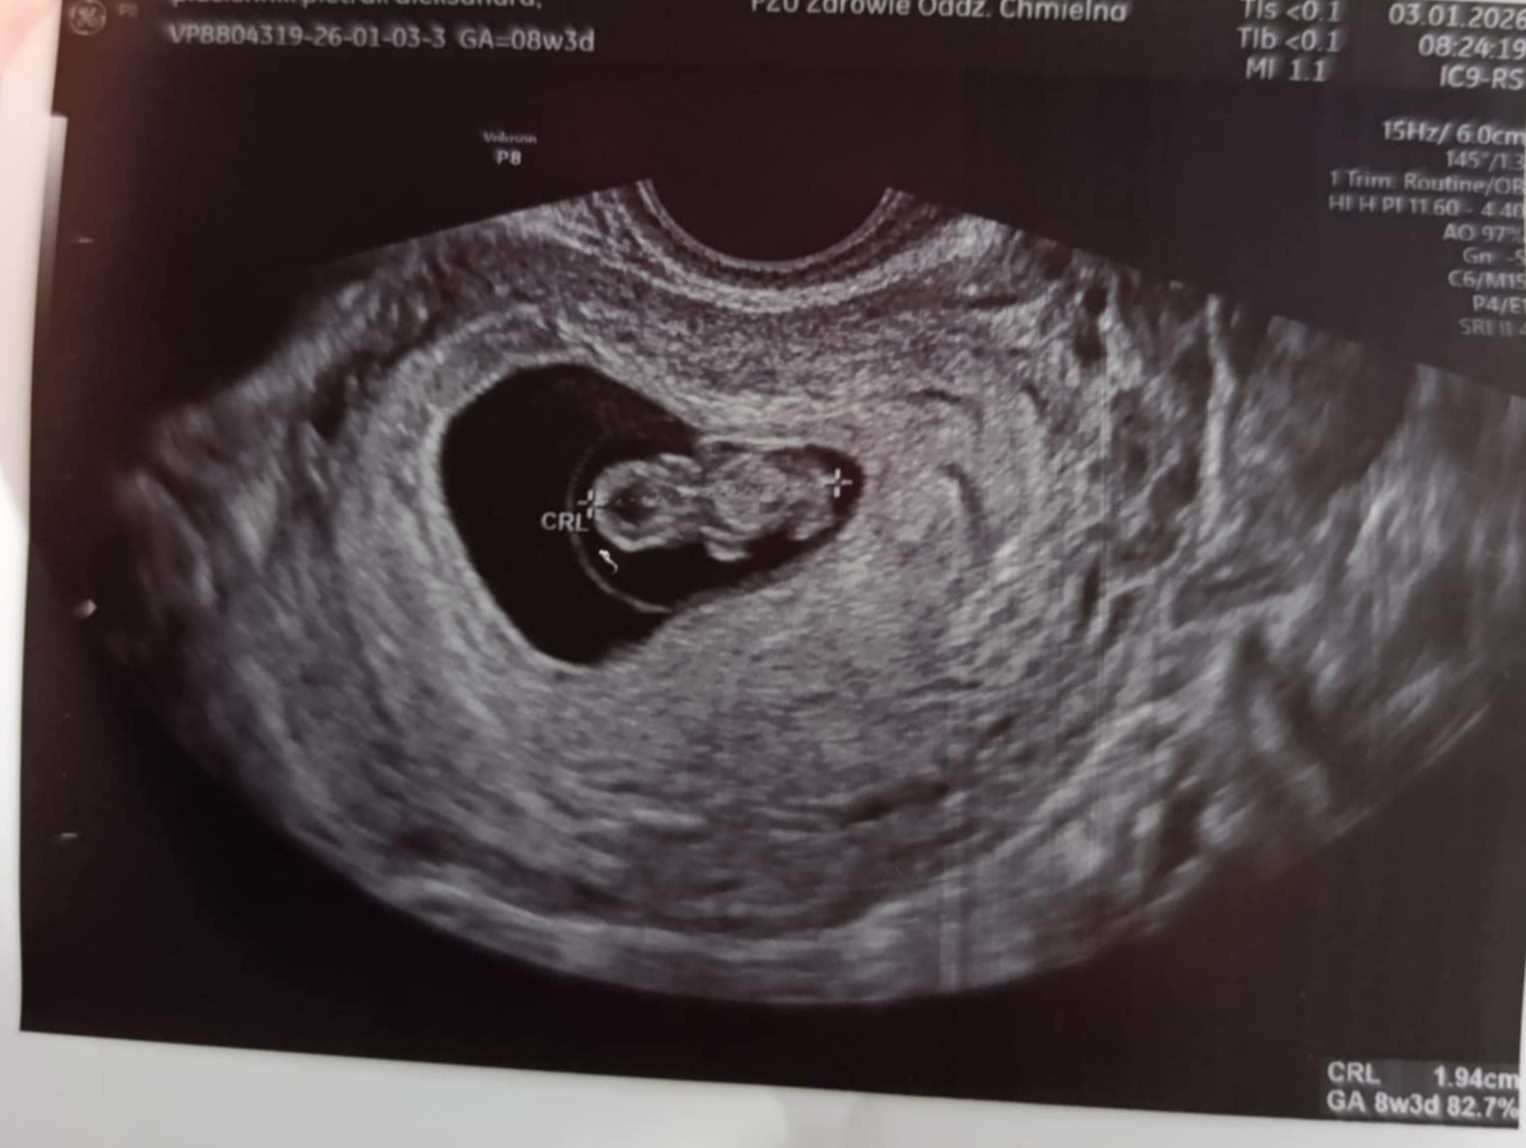

Dzis jak zobaczyłam tego kosmitę na USG to mówię nie no chłopak wygląda jak chłopak